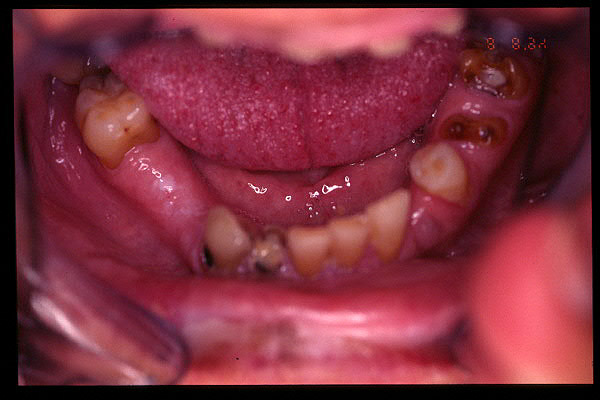

CM Falta de contactos interoclusales

CM Extrusión de incisivos inferiores por falta de contactos oclusales